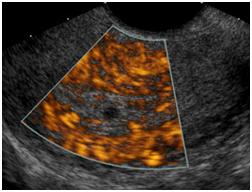

Your doctor has ordered an ultrasound of your pelvis. Ultrasound is a safe and painless procedure that uses sound waves to assess the structure of your internal body organs. The scan can help diagnose such medical conditions as pelvic masses in the uterus and ovaries.

Ultrasound of the Pelvis1